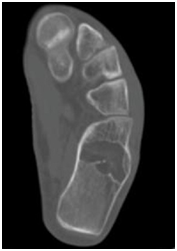

Twenty four year old male presented to us with left heel pain for nine weeks of duration. The onset of the pain was insidious and aggravated by weight bearing and prolonged standing. It was relieved with the use of analgesics and limb rest. There was no history of preceding trauma or rest pain. On examination there was no local swelling and skin changes. Deep tenderness was present over anteromedial aspect of calcaneum. Plain radiographs of the heel revealed well defined, lytic lesion in the calcaneum. Computed Tomographic scan of the same showed lytic lesion in the in the body of calcaneum just below the posterior facet. Provisional diagnosis of benign bone tumor was made and patient was planned for curettage and bone grafting.

Intraosseous lipomas are diagnosed with plain radiography and CT scan (Figure 1) (Figure 2A) (Figure 2B). Mainstay of treatment is conservative; however surgery is indicated in severe pain not responding to conservative treatment, impending pathological fracture and malignant transformation (Figure 3). Treatment for these tumors is curettage and bone grafting (Figure 4) with good prognosis.8–10

Figure 2b CT Scan of the foot, axial view, showing lytic lesion.